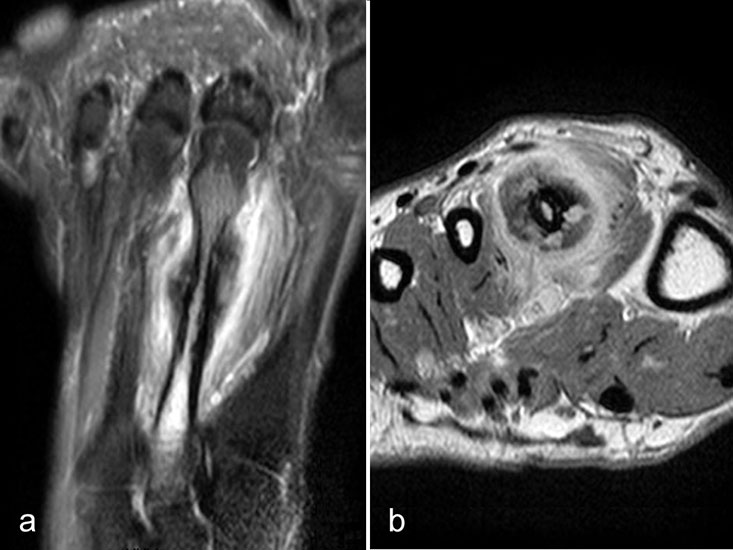

Intermetatarsale Bursitis

Intermetatarsale Bursitis bei rheumatoider Arthritis mit Erguss (a) und deutlicher Synovialitis in mehreren Schleimbeuteln (b).

Abbildung 13

Zwischen den Metatarsaleköpfchen befinden sich kleine Schleimbeutel, die in der Regel MR-tomographisch nicht zu identifizieren sind. Sie werden erkennbar, wenn sie zarte Flüssigkeitsstreifen enthalten, was noch nicht als pathologisch zu werten ist. Eine signifikante Distension und vor allem eine verstärkte Kontrastmittelanreicherung sind Ausdruck einer Bursitis. Die isolierte Bursitis intermetatarsal ist selten und stets hochverdächtig für das Vorliegen einer rheumatischen Grunderkrankung (Abb. 13).

Häufig sind intermetatarsale Bursitiden als Begleitphänomen bei Rupturen oder Degenerationen der plantaren Platte und auch bei Morton-„Neuromen“.